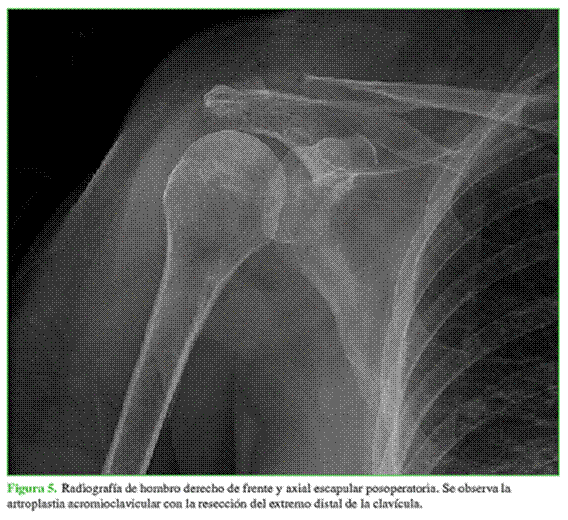

Se repararon los ligamentos acromioclaviculares remanentes y se comprobó la correcta estabilidad articular. Al finalizar la cirugía, se realizó el control radiográfico correspondiente (Figura 5).